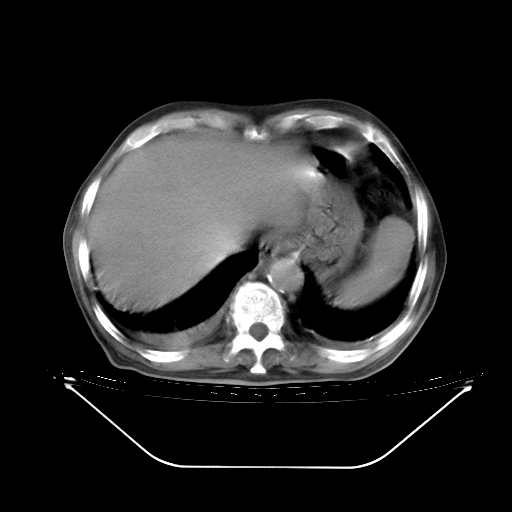

5月9日肺部CT(在4月27日齐鲁医院肺部CT描述部分肺组织磨玻璃样改变,12天后肺组织广泛磨玻璃样改变)

2009年5月9日肺部CT